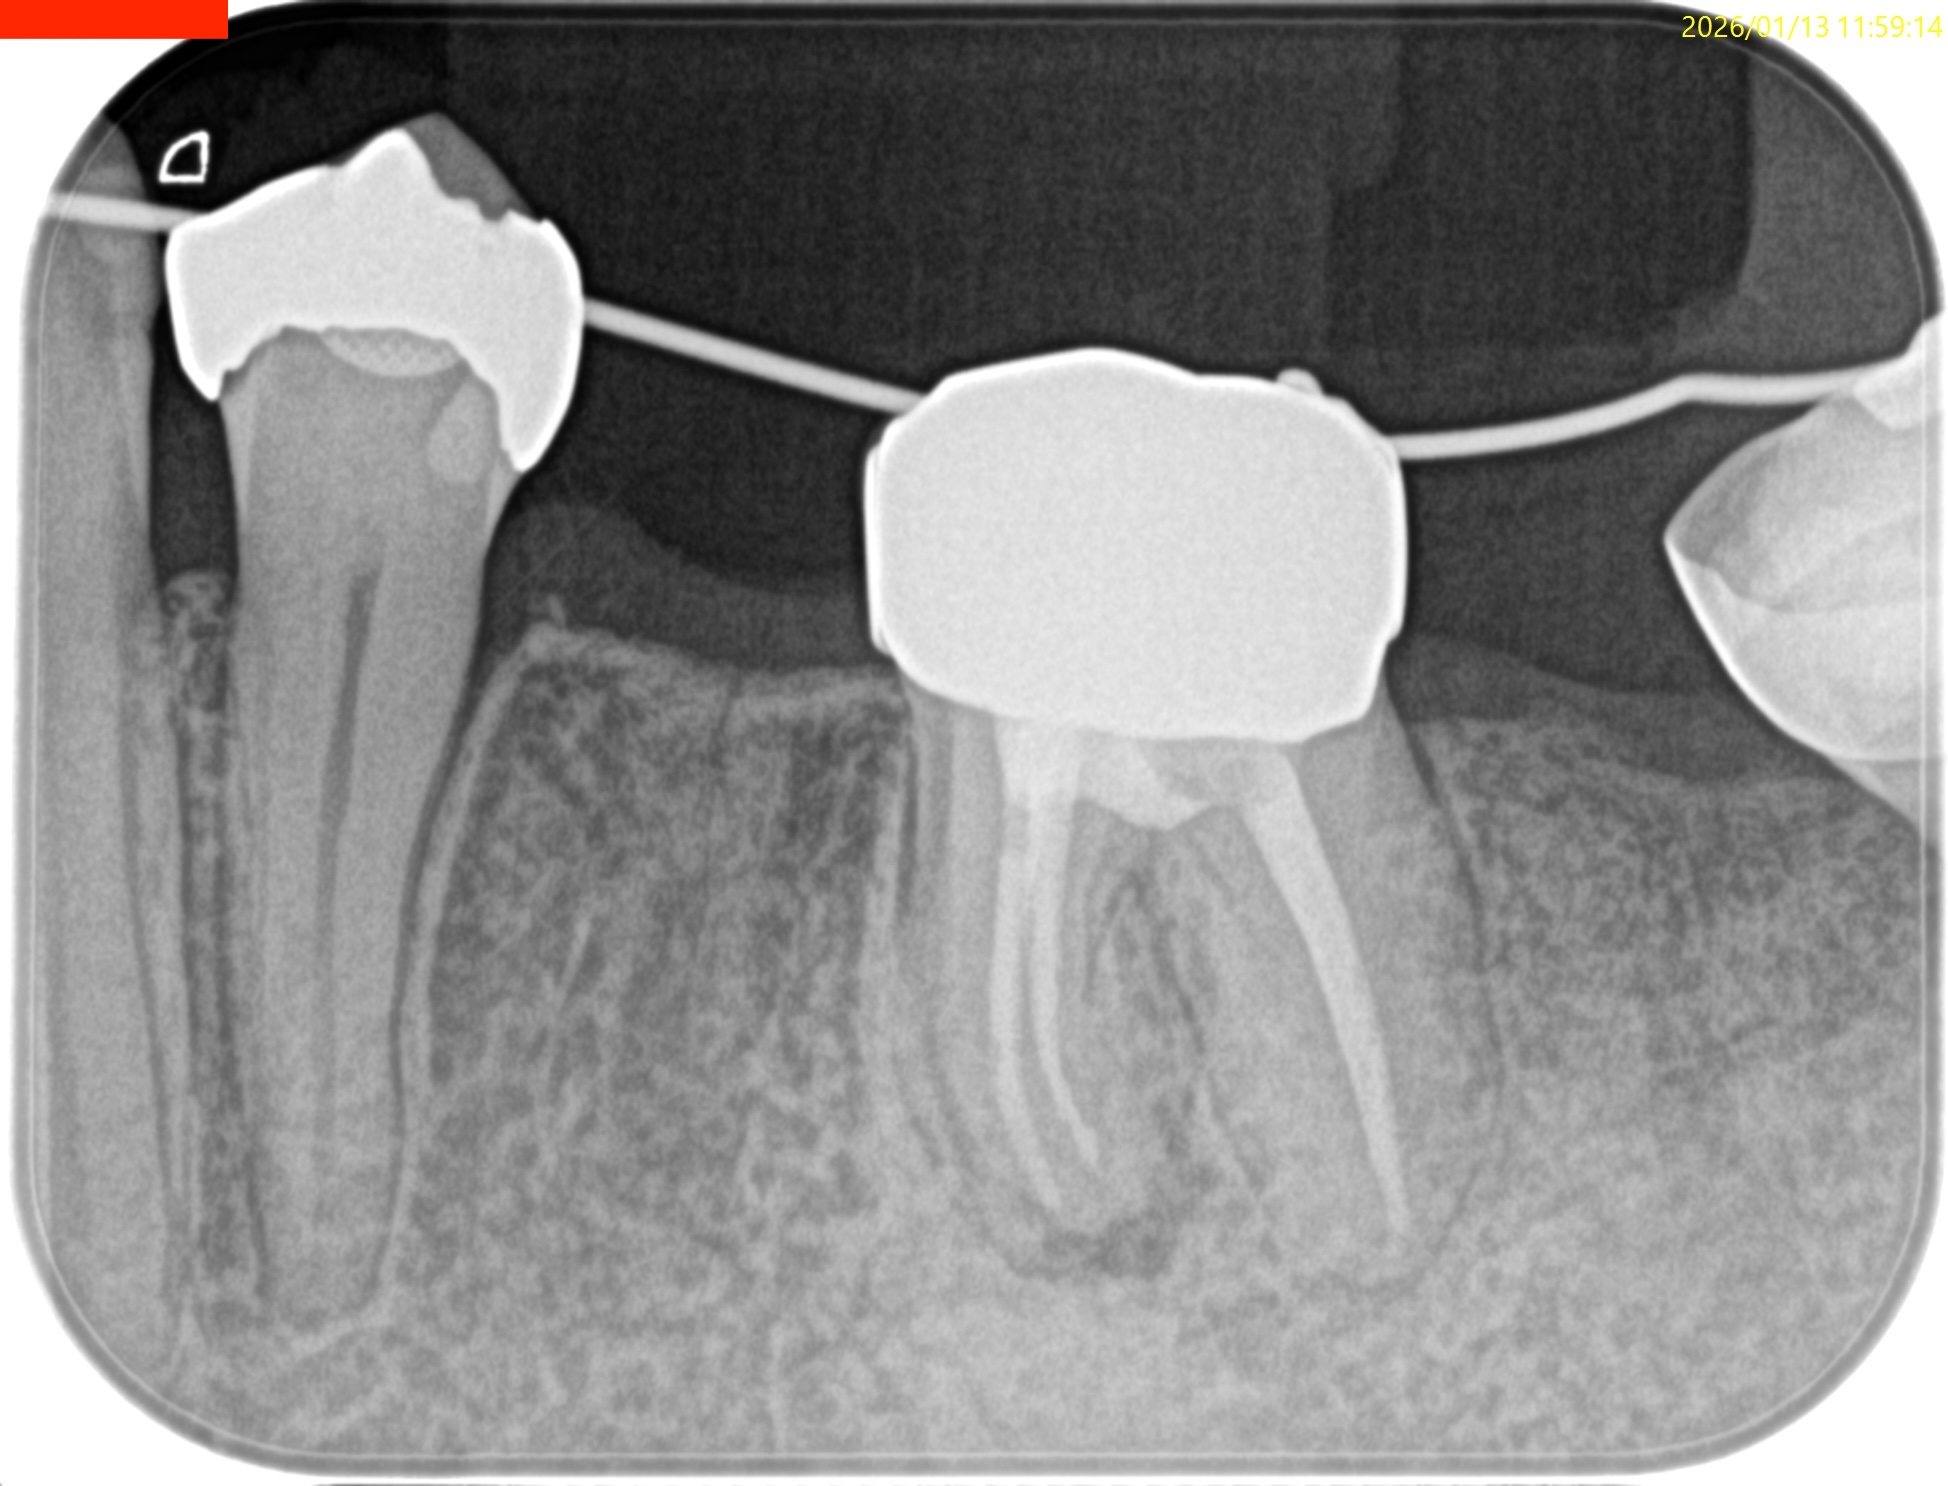

#19 Re-RCT 1yr recall(2026.1.13)

#19

MB

ML

D

術前に大きな根尖病変が存在していたM根のそれは消失はしていないが大幅に縮小し、

術前に根尖病変がなく再根管形成・充填しなかったD根はやはり依然として根尖病変はできていない。

このケースでも

Selective Root Canal Retreatmentが奏功している。

ということで根尖病変は完全消失はしていないのでまた1年後に経過を見せてもらうことになった。